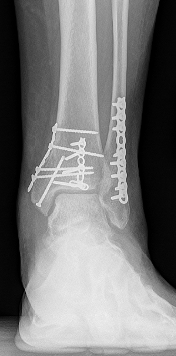

If the ankle fracture is more severe, or if the bones are displaced, i.e. not lined up correctly, surgery may be recommended to fix the fracture. This is called operative treatment. There are several different types of surgery that can be used to fix an ankle fracture, depending on the specific injury.

The most common type of surgery is called an open reduction and internal fixation (ORIF). Incisions are made through the skin to access the broken bone(s). Your surgeon will manually move the bone pieces back into place and hold them in place using special screws or plates. The skin is then closed with stitches. With this treatment, the bones are expected to heal in the proper position.

After surgery, the patient will need to wear a splint or special boot to keep the ankle stable while it heals. Putting weight on the leg may be restricted until up to 6 weeks after surgery. Physical therapy may also be recommended to help the person regain strength and mobility in the ankle.